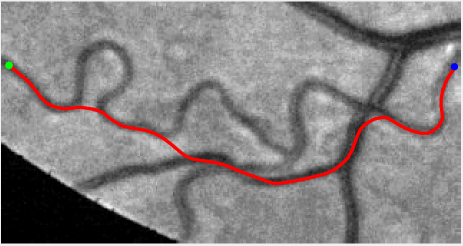

Validation. We validate our minimal path model on respective 54 and 30 patches obtained from the DRIVE [14, 15] and the IOSTAR [16] datasets with AV groundtruth. Each artery involved in these parches locates near a vein or crossing it at least once. Our goal is to extract the artery between two given points. In order to get the quantitative evaluation, we first convert each continuous spatial path to an 4-connected digital path which is considered as a pixel collection. We denote by the collection of digital path pixels inside the artery groundtruth map . Thus, a measure can be simply defined as , where and mean the respective number of elements involved in and . We compare our model to four existing minimal path models: the isotropic Riemannian (IR) model [1], the anisotropic radius-lifted Riemannian (ArR) model [4], the isotropic orientation-lifted Riemannian (IoR) model [5] and the curvature-penalized (CuP) model [7]. The construction of these metrics are based on the OOF outputs [12]. Note that a centerline-based potential is chosen so that we remove the radius dimension of [5] to reduce computation complexity. The results in terms of the score are presented in Table 1, including the average (Avg.), maximum (Max.), minimum (Min.) and standard deviation (Std.) values. In both DRIVE and IOSTAR datasets, our method can achieve the best performances thanks to the coherence penalization. Note that in Table 1, we evaluate our method by using the refined paths instead of using the original coherence-penalized minimal paths. For comparisons in visualization, we show the minimal paths from the ArR metric , the CuP metric and the proposed coherence-penalized metric on three retinal patches as shown in Fig. 3. The targeted artery vessels which cross veins at least once are labeled by red color in column 1. The paths shown in column 4 from the proposed metric are results after refinement. One can claim that our method indeed can catch expected arteries while other metrics fall into the traps of short branches combination.